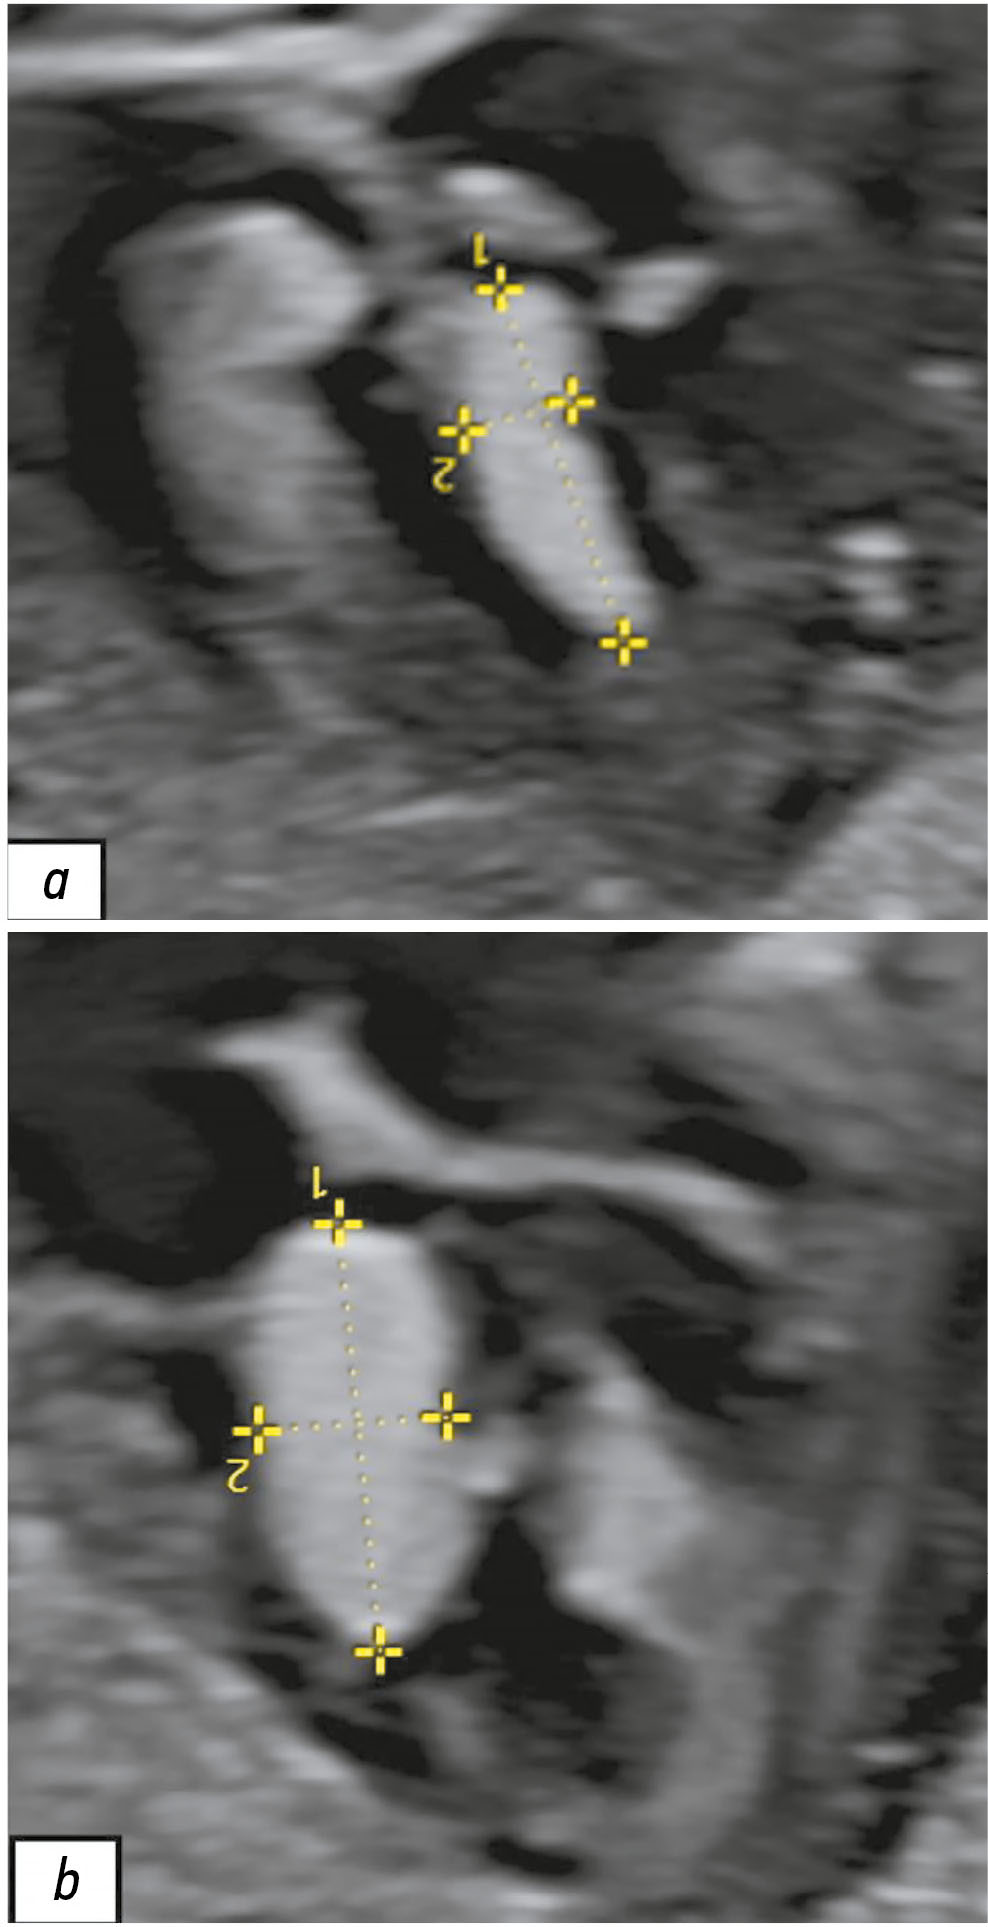

Magnetic resonance imaging in prenatal diagnosis of tuberous sclerosis complex: a case report

Early detection of orphan diseases, including tuberous sclerosis complex, requires a multidisciplinary approach and the integration of new prenatal diagnostic methods, utilizing ultrasound and magnetic resonance imaging. Accumulated knowledge of the clinical manifestations of tuberous sclerosis complex and advancements in diagnostic techniques enable the identification of this condition. Magnetic resonance imaging allows for high-quality anatomical and functional imaging of the brain in various planes, improving the sensitivity and diagnostic value of the method for early (prenatal) detection of cerebral manifestations of tuberous sclerosis complex. Additionally, magnetic resonance imaging detects mediastinal masses. This highlights the need for a comprehensive approach in diagnosing tuberous sclerosis complex, with magnetic resonance imaging as the primary method for assessing the fetus’s cardiovascular and central nervous systems.

This article presents a clinical case of tuberous sclerosis complex determined by intrauterine diagnosis followed by postnatal examination of the newborn and genetic confirmation of the diagnosis. This case report demonstrates the diagnostic value of magnetic resonance imaging in the prenatal diagnosis of tuberous sclerosis complex.